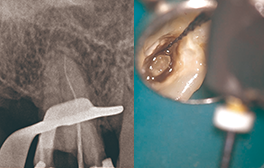

Case1 湾曲根管

• CC「左下奥違和感」主訴に来院

• 左下⑤6⑦Br除去→左下7 2次カリエス認める

• 湾曲大きく穿通せず…ハンドファイルで治療回数5回

EdgeSequel Sapphire™#15/.06テーパーにてグライドパス形成

• 作業長確認

最終拡大#40/.04テーパー